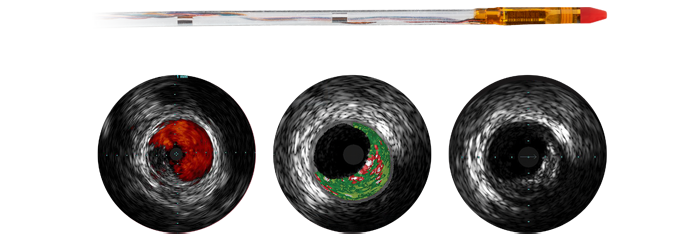

Image-guided therapy, iFR, IVUS and haemodynamic monitoring, as well as cardiac pre-procedure planning and advanced applications, are all connected to the image-guided therapy interface to allow viewing, manipulation and custom configuration on the monitor from a single controller at table side or from the control room.